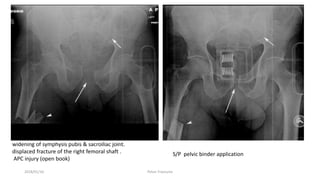

widening of symphysis pubis & sacroiliac joint.

displaced fracture of the right femoral shaft .

APC injury (open book)

S/P pelvic binder application